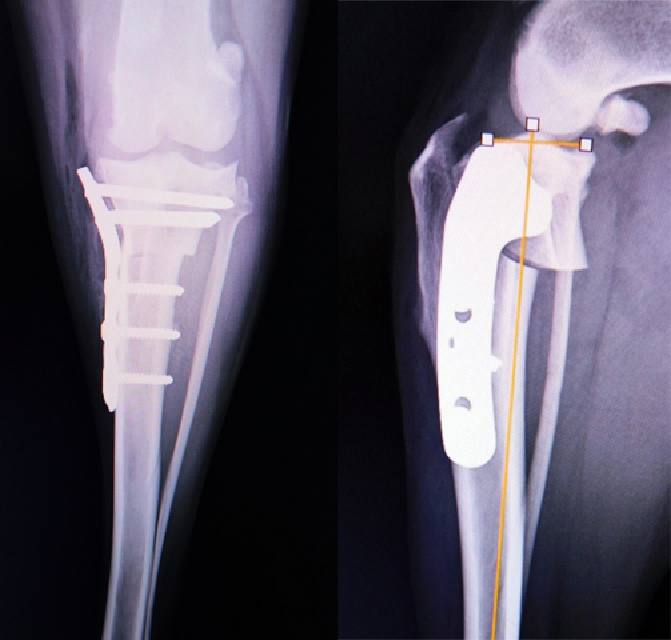

TPLO(脛骨高平部水平骨切り術)

膝下の脛骨を扇状に切断し、尾側に移動することで関節内の脛骨と大腿骨を正常な位置に戻し特殊なプレートで固定します。

大腿骨と脛骨の位置関係が整復されることで負重する時の膝の動きが安定化して跛行が改善します。

当院では2㎏のチワワから70㎏の超大型犬までTPLOを行っています。

【術前】大腿骨遠位端骨折プレート整復固定 -

【術後】大腿骨遠位端骨折プレート整復固定 -

【術前】大腿骨粉砕骨折プレート整復固定 -

【術後】大腿骨粉砕骨折プレート整復固定 -